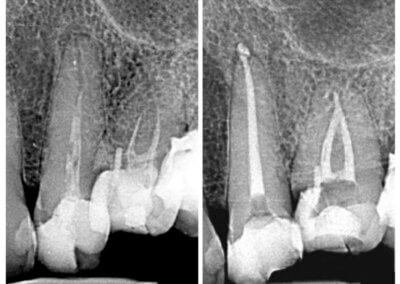

Endodonția este o ramură esențială a stomatologiei, axată pe diagnosticarea, prevenirea și tratamentul afecțiunilor pulpei dentare și a țesuturilor periapicale. Această specialitate joacă un rol crucial în salvarea dinților naturali, evitând extracțiile și menținând sănătatea orală pe termen lung. Prin tehnici avansate și echipamente de ultimă generație, endodonția asigură tratamente precise și eficiente, contribuind la redarea sănătății și funcționalității dinților într-un mod durabil și predictibil.

Utilizarea tehnicilor moderne asigură un tratament rapid, precis și confortabil pentru pacient.